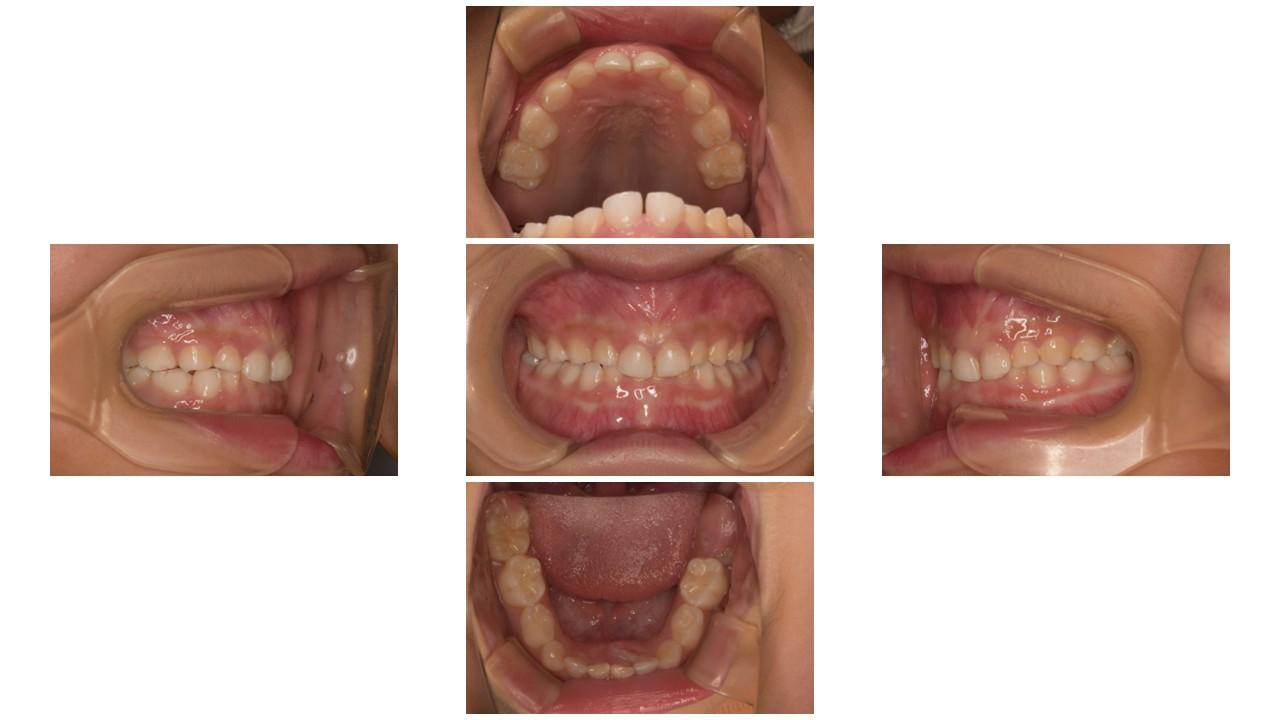

「叢生」は、一般的に「乱ぐい歯(らんぐいば)」「八重歯(やえば)」「ガタガタの歯並び」などと呼ばれる状態で、日本人に非常によく見られる不正咬合(ふせいこうごう:良くない噛み合わせ)です。

<叢生の状態>

顎(あご)の骨の大きさに対して、歯のサイズが大きすぎたり、歯が並ぶスペースが不足していたりするために、歯がデコボコに重なり合って生えている状態を指します。